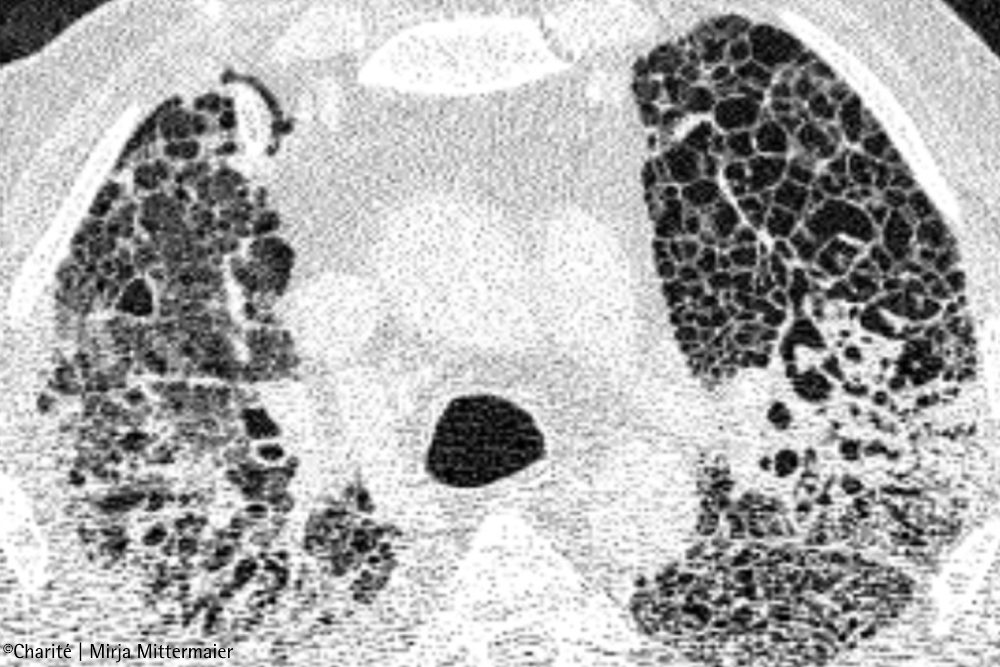

Für die Studie untersuchte das Team die Lungen verstorbener COVID-19-Patient:innen anhand verschiedener mikroskopischer Aufnahmen. „Bei fast allen Betroffenen haben wir enorme Schäden entdeckt: Die Lungenbläschen waren weitgehend zerstört, die Wände deutlich verdickt. Außerdem fanden wir ausgeprägte Ablagerungen von Kollagen, welches ein Hauptbestandteil von Narbengewebe ist. All dies ist charakteristisch für eine schwere Fibrose“, beschreibt Prof. Dr. Peter Boor die Befunde. Er hat die Studie am Institut für Pathologie der Uniklinik RWTH Aachen geleitet. „Diese Beobachtungen weisen darauf hin, dass wir es beim COVID-19-Lungenversagen mit einem sogenannten fibroproliferativen ARDS zu tun haben, also einer besonders schweren Form des Lungenversagens. Das könnte erklären, warum wir die Betroffenen so lange beatmen müssen.“

„Unsere Daten zeigen also eindeutig Parallelen zwischen COVID-19 und der chronischen Lungenfibrose auf“, resümiert Dr. Saliba. „Das erklärt vielleicht, warum einige Risikofaktoren für COVID-19 auch Risikofaktoren für die idiopathische Lungenfibrose sind – zum Beispiel Grunderkrankungen, Rauchen, ein männliches Geschlecht und ein Alter über 60 Jahre. Es gibt jedoch einen entscheidenden Unterschied zwischen den beiden Erkrankungen: Bei COVID-19 ist die Vernarbung zumindest potenziell reparabel.“ Das konnte das Forschungsteam anhand von CT-Bildern nachvollziehen. Bei COVID-19-Erkrankten, die mit der ECMO behandelt wurden, zeigten die Aufnahmen zunächst typische milchglasartige Trübungen, die sich im Verlauf der Erkrankung verdichteten und vernarbten. Bei Betroffenen, die von der ECMO-Behandlung entwöhnt werden konnten und genasen, gelang es dem Körper, die Verdichtungen allmählich aufzulösen – auch wenn in manchen Fällen deutliche Vernarbungsreste zurückblieben.